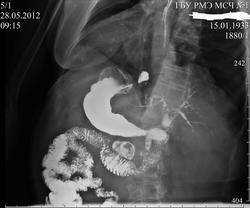

Рентгеноскопия - дивертикул 12 перстной.

Женщина с жалобами на тошноту и рвоту почти ежедневно. На ФГДС чисто, послали ко мне. Желудок и пищевод подозрений особых не вызвали, зато 12 перстная.... с таким первый раз столкнулся. Мое мнение - дивертикул 12 п.к.

Эта круглая тень действительно дивертикул. Вы четко просмотрели пассаж по 12-перстной кишке? Перед указанным дивертикулом есть небольшой участок неравномерного контрастирования просвета, там, где может проходить верхняя брыжеечная артерия. Синдром сдавления не всегда дает ярчайшую клиническую картину, а рентгенпризнаки есть.

Дивертикулы 12-ти перстной кишки.

Пациентка 1933г. Жалобы на эпизоды давящих болей в эпигастирии. В анамнезе холецистэктомия.